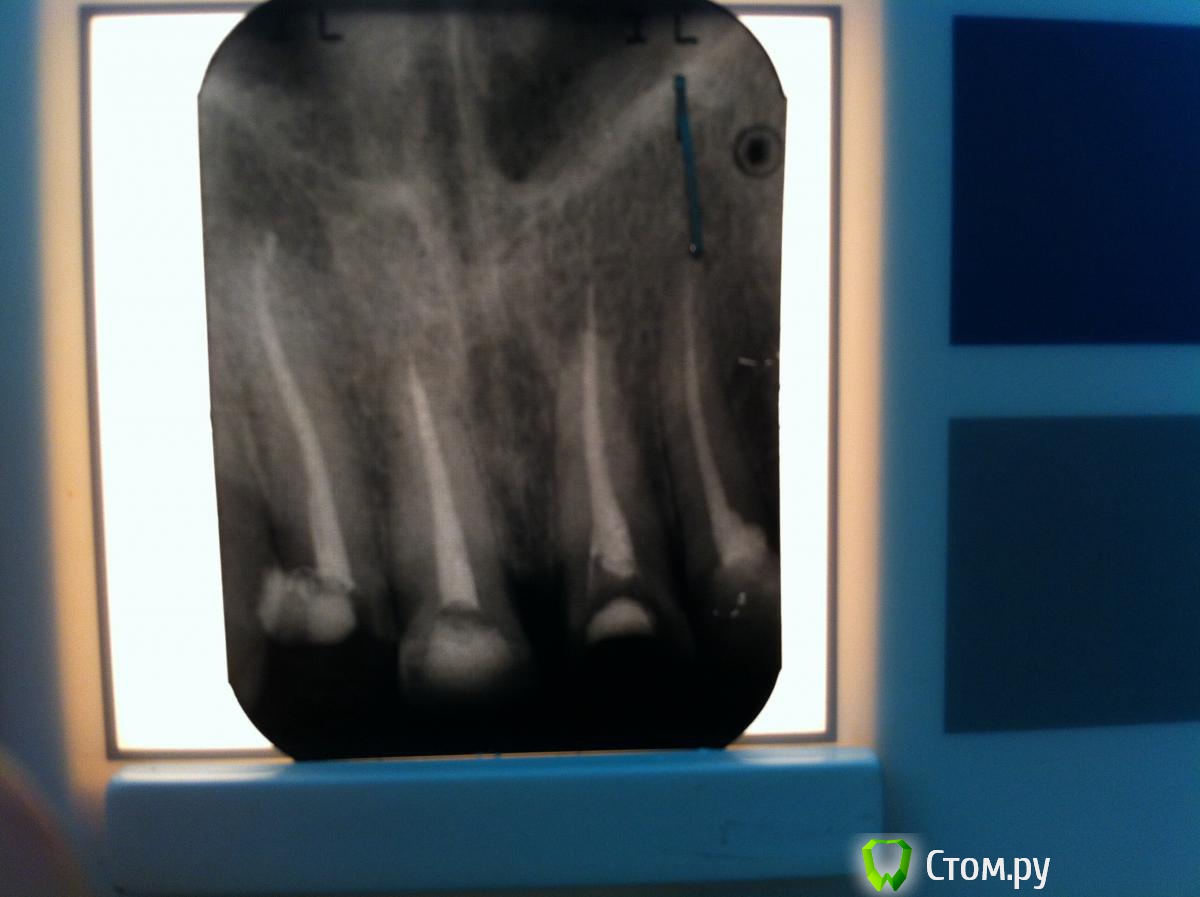

kukolenOk Опубликовано 20 ноября, 2013 Поделиться Опубликовано 20 ноября, 2013 (изменено) Нет, только зеркало с родиевым покрытием ,недавно купил. Зрение 1.0 Скоро,надеюсь,возьму лупы- хоть что-то. Спасибо,стараемся Я бы так не делал. Латералить желательно только 0.2 конусом. Снимки, как обещала Изменено 20 ноября, 2013 пользователем kukolenOk Ссылка на комментарий